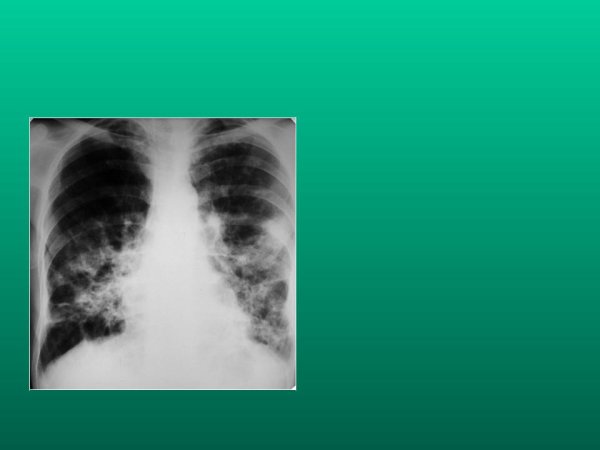

Деформированный легочный рисунок - это состояние, при котором наблюдается изменение обычного внешнего облика легких на рентгенограмме. Такое отклонение может быть связано с различными заболеваниями и патологическими процессами, такими как хронические обструктивные заболевания легких, фиброз, опухоли или воспалительные процессы. Деформированный легочный рисунок может представлять собой уменьшение объема легочной ткани, нарушение архитектуры легочных сосудов или изменение контуров легочных полей. Раннее выявление и диагностика таких изменений могут помочь в раннем начале лечения и улучшении прогноза для пациента.

Синдром деформации легочного рисунка